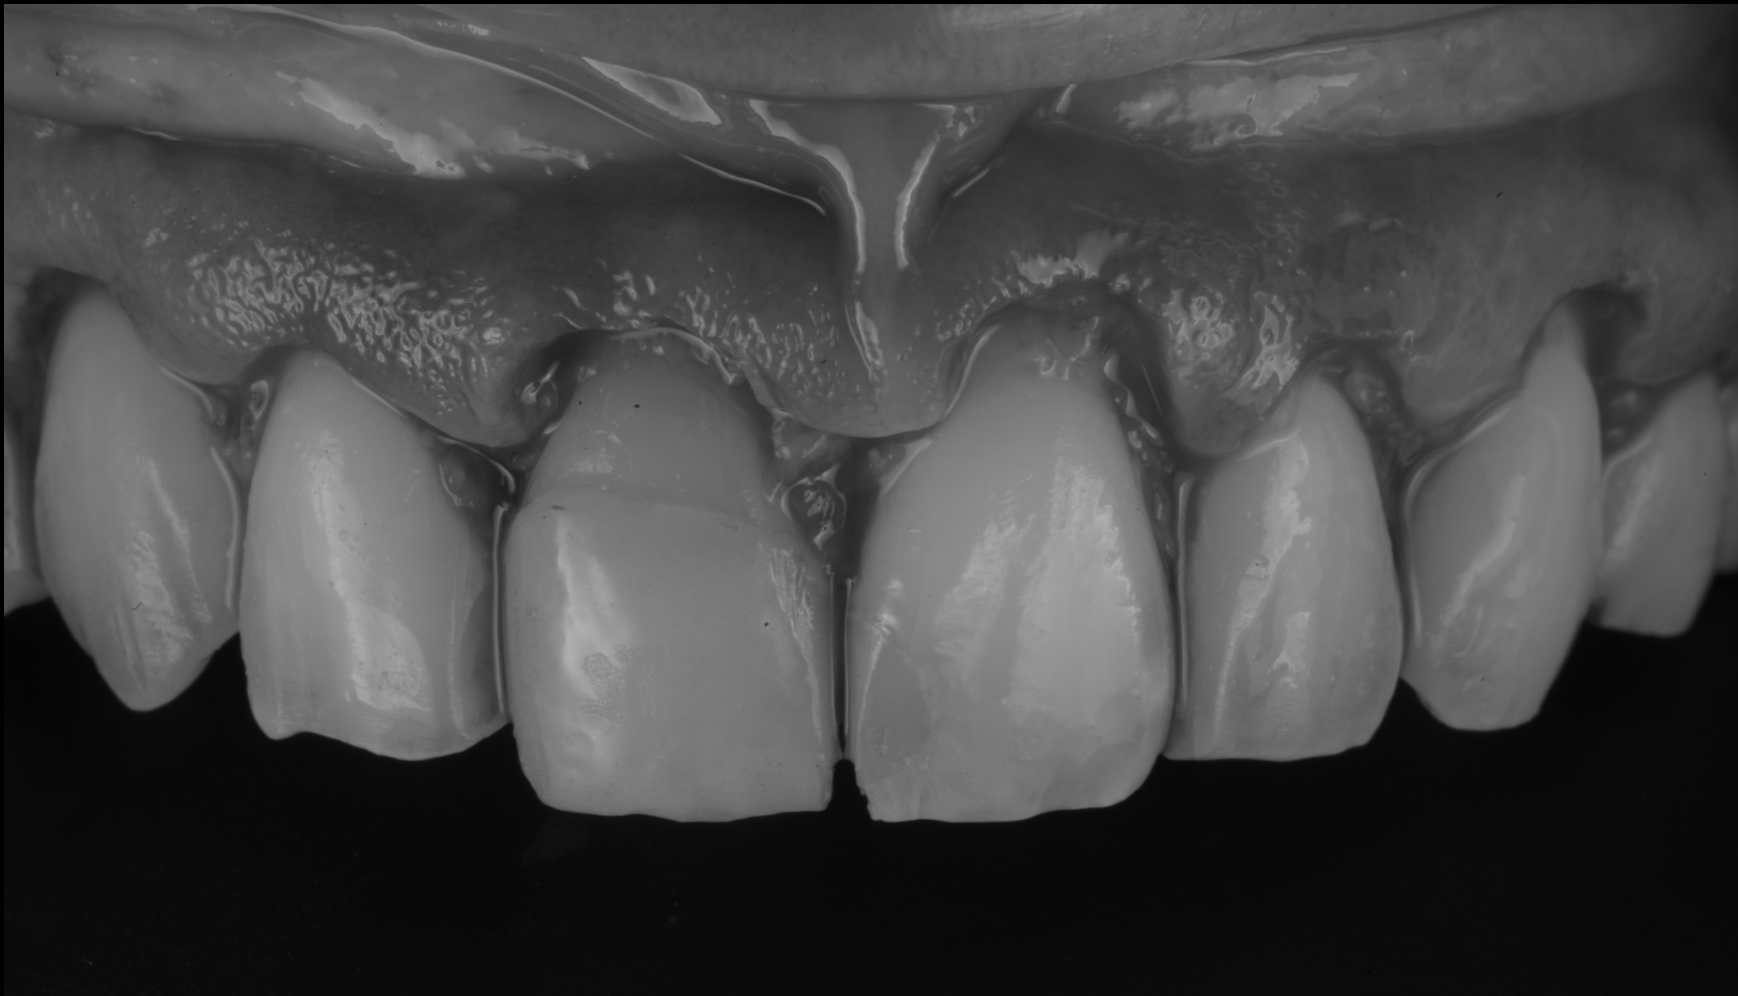

矯正終了後(クラウンレングスニング)

術中(クラウンレングスニング)

Step2:クラウンレングスニング(歯冠長延長術)

矯正で歯並びが整うと、次に気になるのが

歯の長さ・左右差・歯ぐきラインです。

クラウンレングスニングでは、

• 歯ぐきのラインを整える

• 必要に応じて骨の位置(生物学的幅径)も考慮して安定させる

ことで、セラミックの仕上がりだけでなく、清掃性・再発リスクも含めて整えます。